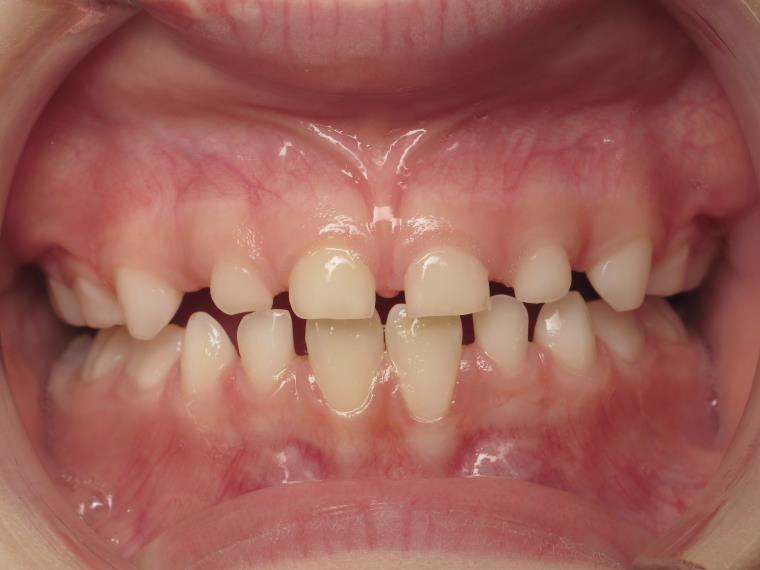

12 béance inversé droit 4 ans

inversion postérieur coté droit et espace entre les dents du haut et du bas (diastèmes)

appareillage mobile pendant 35 mois